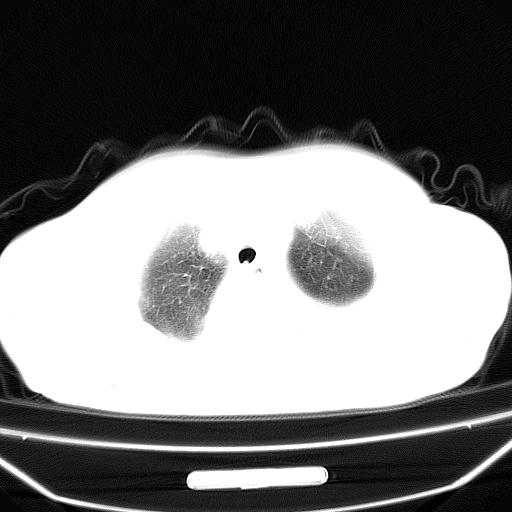

以下是引用jiangjing在2008-4-20 10:43:00的发言:[br]结合病史支持 冠心病[冠状动脉钙化],心功能不全,肺淤血、肺水肿,双侧胸腔与斜裂积液

以下是引用liuyue在2008-4-19 22:25:00的发言:[br]先考虑:1.心衰伴肺水肿、双侧胸腔积液、叶间积液、双下肺不完全性肺不张; [br] 2.冠状动脉粥样硬化。